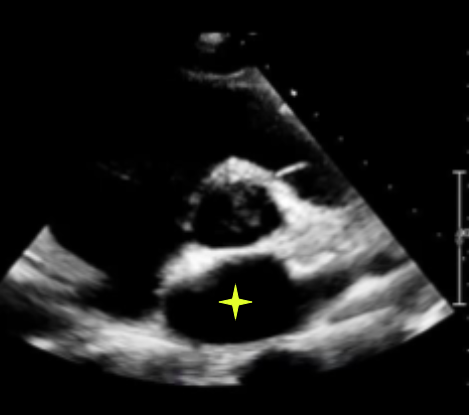

normal or grade 2 (pseudonormal)